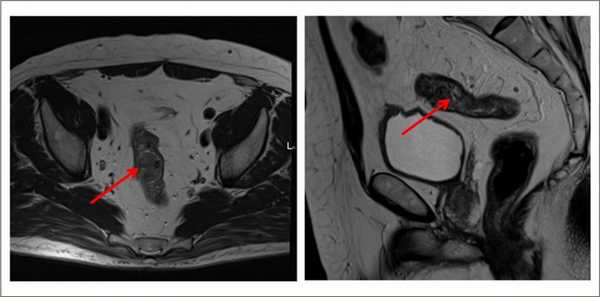

В диагностике рака анального канала широко используется магнитно-резонансная томография (МРТ). Этот безопасный с точки зрения облучения метод позволяет оценить степень инвазии (распространения) опухоли на окружающие структуры, а также заподозрить наличие метастатических лимфатических узлов.

С целью уточнения распространенности опухолевого процесса в малом тазу, а именно выхода опухоли за пределы стенки кишки, выявления метастазов в лимфатических узлах, применяют дополнительные методы исследования (трансректальное ультразвуковое исследование, компьютерная томография, магнитно-резонансная томография, лапароскопия).

Выявляет даже небольшие по размеру патологические очаги, метастазы и инвазию опухоли в соседние органы, ее топографическое положение относительно других структур. Метод безопасен, не создает радиационную нагрузку, в отличие от КТ.